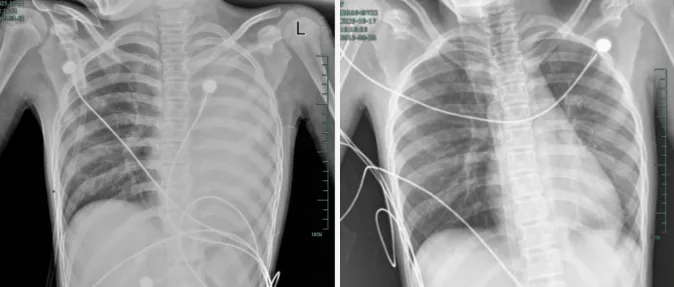

治疗前后影像对比,左肺从“白肺”到正常状态。

据介绍,笑笑一开始只是轻微咳嗽,发热到38℃,检查提示肺炎、肺不张。转诊到浙大四院儿科时,病情急剧恶化,出现呼吸急促、胸闷胸痛,体温38.5℃,只能靠5L/min的面罩吸氧维持血氧,胸片显示左肺已完全呈“白肺”改变,肺部炎症进展迅猛。